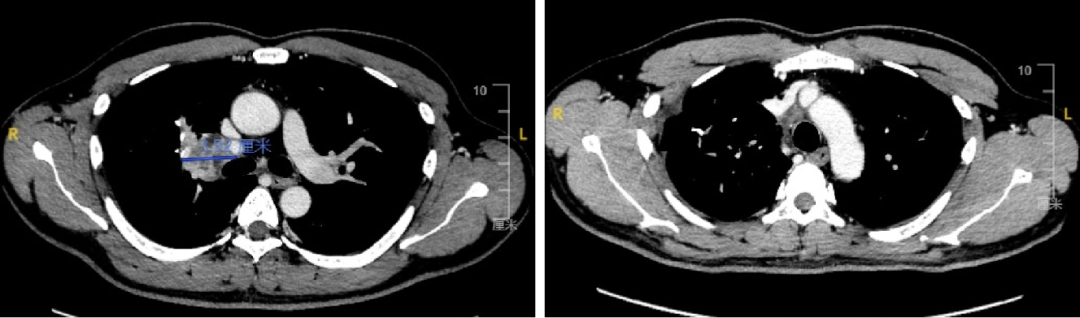

C2程后影像学评估为SD,C4程前为PR。

图片6.png

图3 病灶1影像学评估

图片7.png

图4 病灶2影像学评估